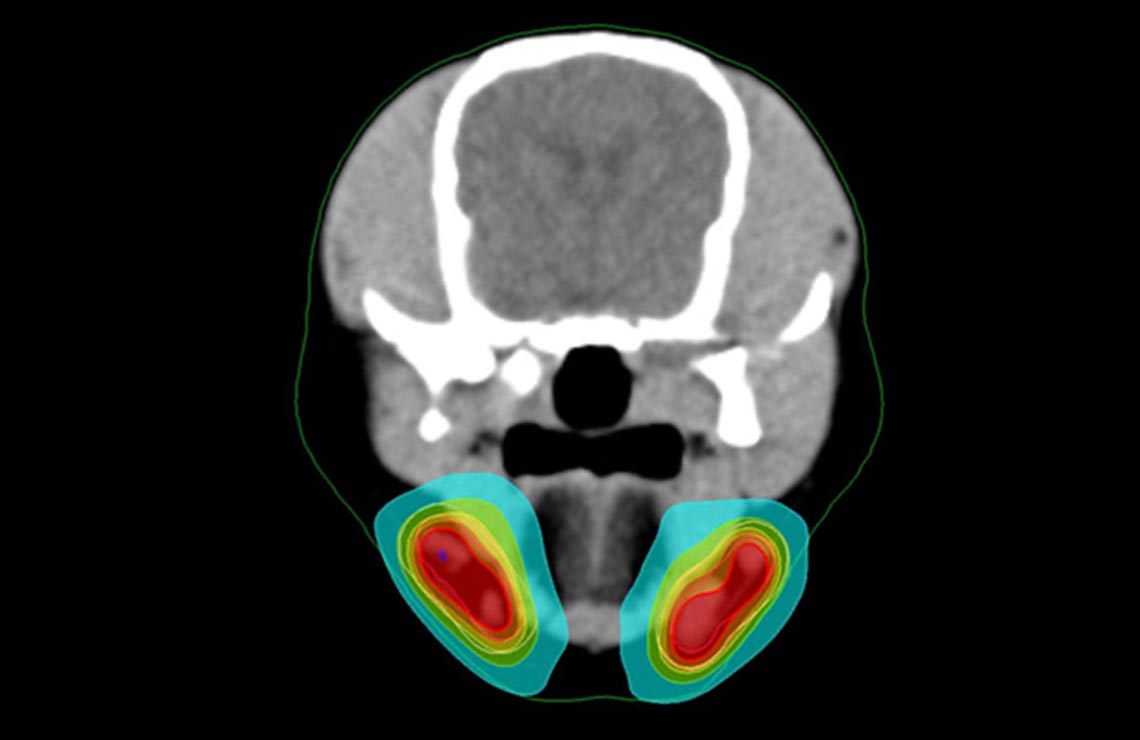

また、3-5個程度までの肺転移やリンパ節転移病変に対して同時に治療することも可能です。